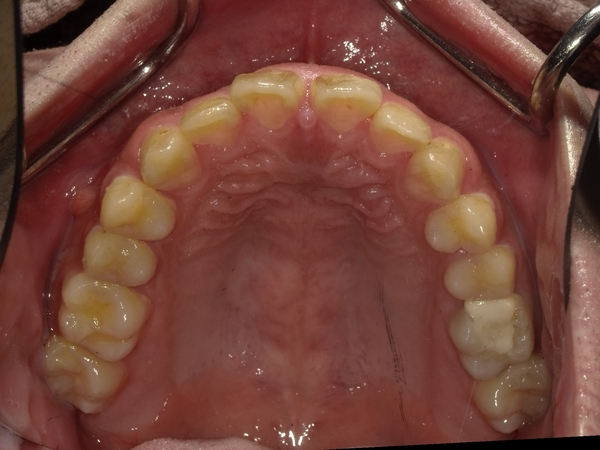

すきっぱ(空隙歯列)CASE7 2023.08.28 20代男性☆Before→After☆〇ご相談内容:前歯真ん中の隙間があいている〇矯正の種類:マウスピース型矯正「インビザラインGO」〇治療期間:19週間〇治療費用:44万円(税込) < すきっぱ(空隙歯列)CASE8すきっぱ(空隙歯列)CASE6 > ブログ記事一覧をみる